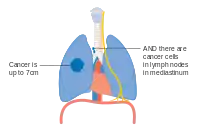

- المرحلة الثالثة - عند انتشار الورم إلى غدد لمفاوية بعيدة.

المرحلة AIII من سرطان الرئة

المرحلة IIIA من سرطان الرئة

المرحلة IIIB من سرطان الرئة